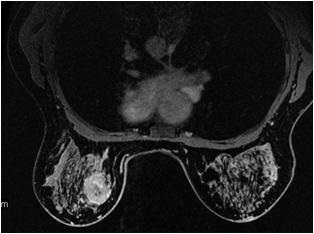

VIBRANT with Flex Imaging Option

VIBRANT (Volume Imaging for BReast AssessmeNT) with Flex Imaging Option is a single slab 3D, dual echo, Fast SPGR application that acquires out-of-phase and in-phase echoes used to generate fat and water images using a two-point Dixon technique. The VIBRANT with Flex is compatible with Breast coils and can be used for either bilateral or unilateral breast imaging.

To shorten scan time, VIBRANT with Flex uses a partial fourier acquisition technique and ARC. It also uses a high receive bandwidth to minimize chemical shift effects and to acquire the first out-of-phase and in-phase echoes within the same TR.